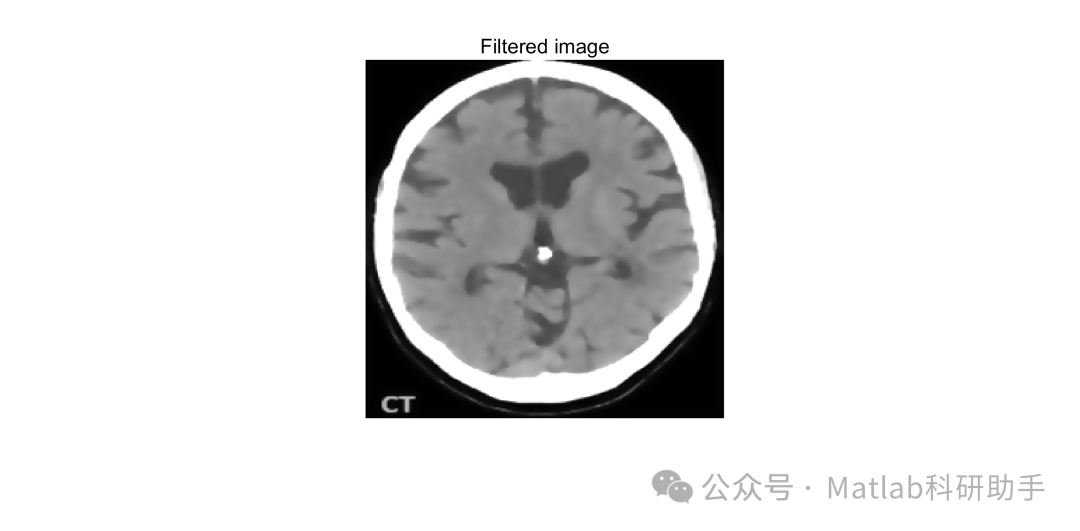

- 各向异性滤波去噪:对预处理后的图像应用 Perona-Malik 等各向异性滤波算法,抑制噪声并保留肿瘤边缘。

⛳️ 运行结果